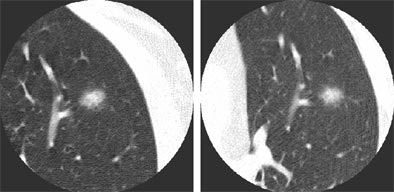

![]() |

| Non-solid nodule at baseline (left) and follow-up (right). |